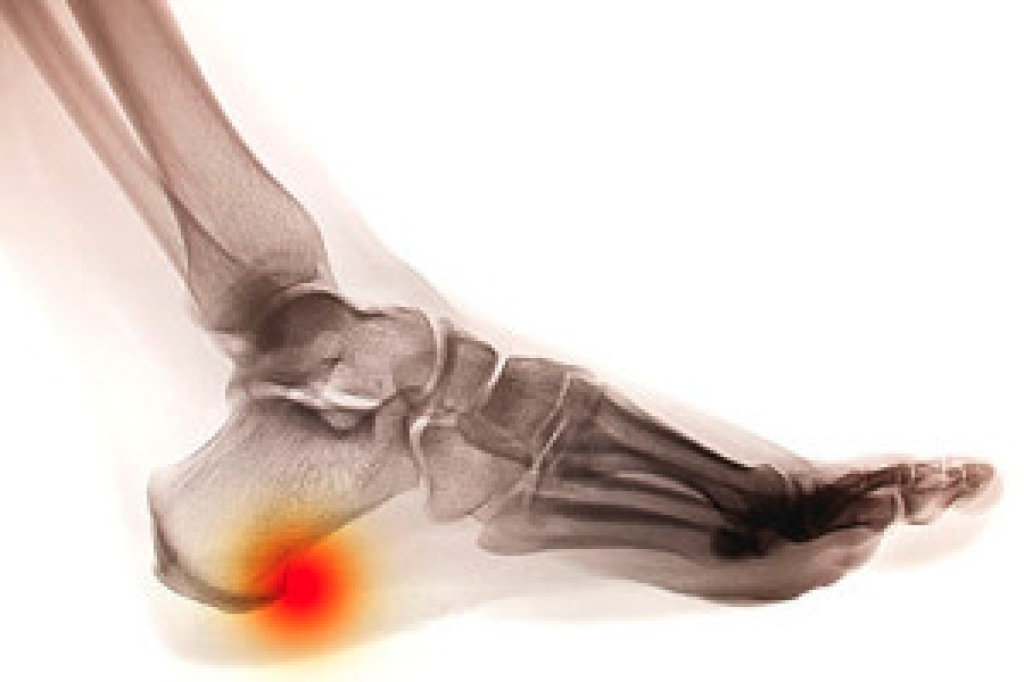

Peripheral neuropathy affects the nerves in the feet, often leading to unusual sensations that can develop gradually. Patients may notice burning, tingling, numbness, or a pins and needles feeling, especially in the toes or soles. The skin may appear normal, but the loss of sensation can make it difficult to detect injuries, increasing the risk of unnoticed wounds. Some individuals also experience sharp or shooting pain, particularly at night. Common causes include diabetes, nerve compression, certain medications, or underlying medical conditions that affect nerve health. A podiatrist can evaluate nerve function through a detailed exam and may recommend additional testing to determine the cause. Treatment focuses on managing symptoms, protecting the feet, and improving nerve health with medication, supportive footwear, and targeted exercises. Early attention is important to prevent complications. If you have symptoms of peripheral neuropathy, it is suggested that you make an appointment with a podiatrist.

To treat neuropathy in the foot, podiatrists will first diagnose the cause of the neuropathy. Figuring out the underlying cause of the neuropathy will allow the podiatrist to prescribe the best treatment, whether it be caused by diabetes, toxic substance exposure, infection, etc. If the nerve has not died, then it’s possible that sensation may be able to return to the foot.

Pain medication may be issued for pain. Electrical nerve stimulation can be used to stimulate nerves. If the neuropathy is caused from pressure on the nerves, then surgery may be necessary.